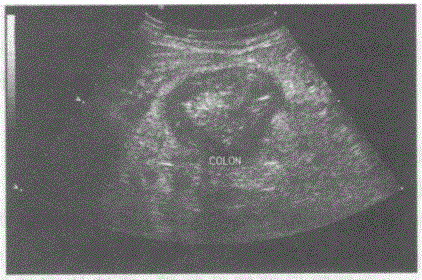

问题 临床资料:男,62岁,自述右下腹痛,便血。 化验检查:便潜血阳性。 超声综合描述:右下腹扫查升结肠起始段可见假肾样回声区,肠壁不均匀增厚,厚度0.81.2cm。 超声提示:

选项 A.结肠正常声像图 B.结肠炎 C.阑尾炎 D.结肠癌

答案 D